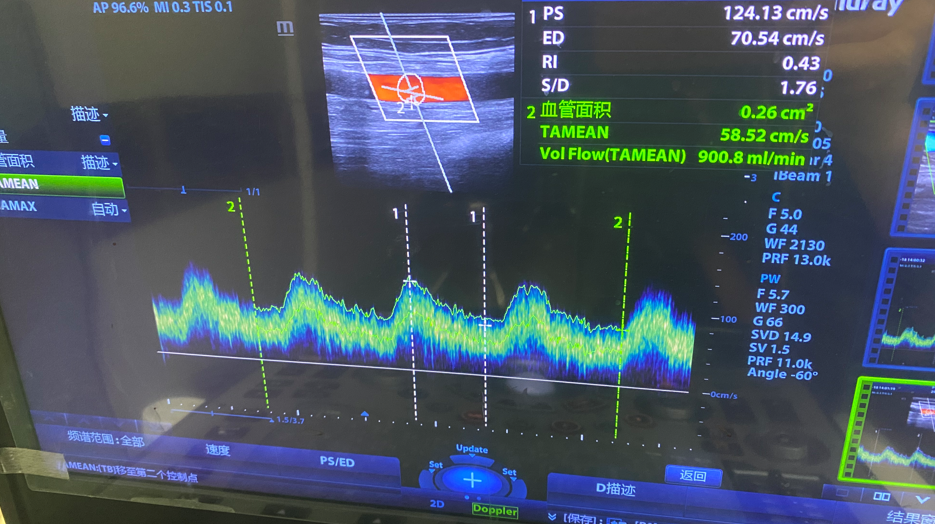

术后肱动脉血流量900ml/min